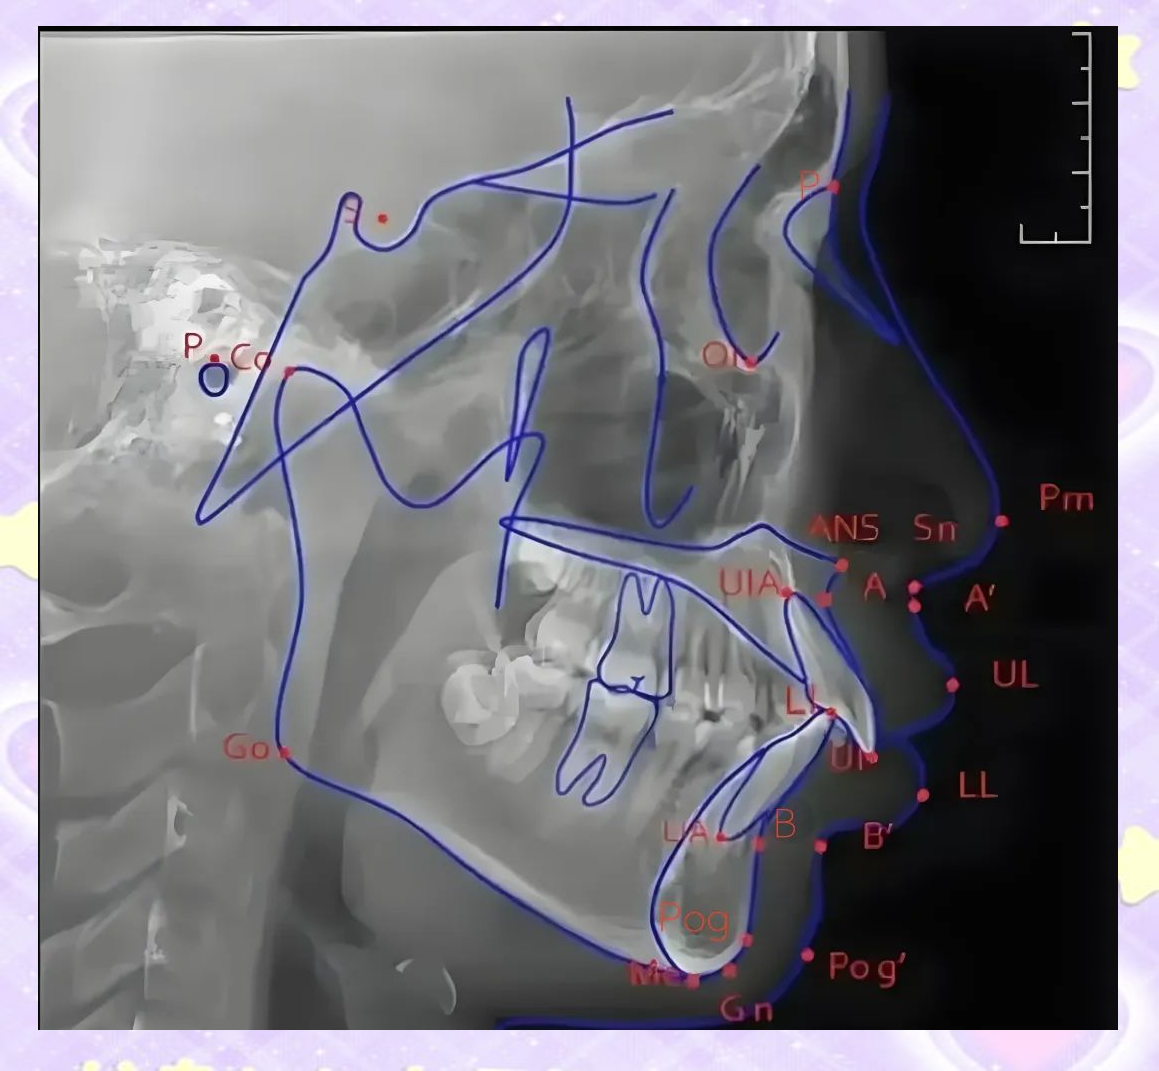

头影测量中如何准确找到标记点

颅部和软组织侧面头影测量标志点